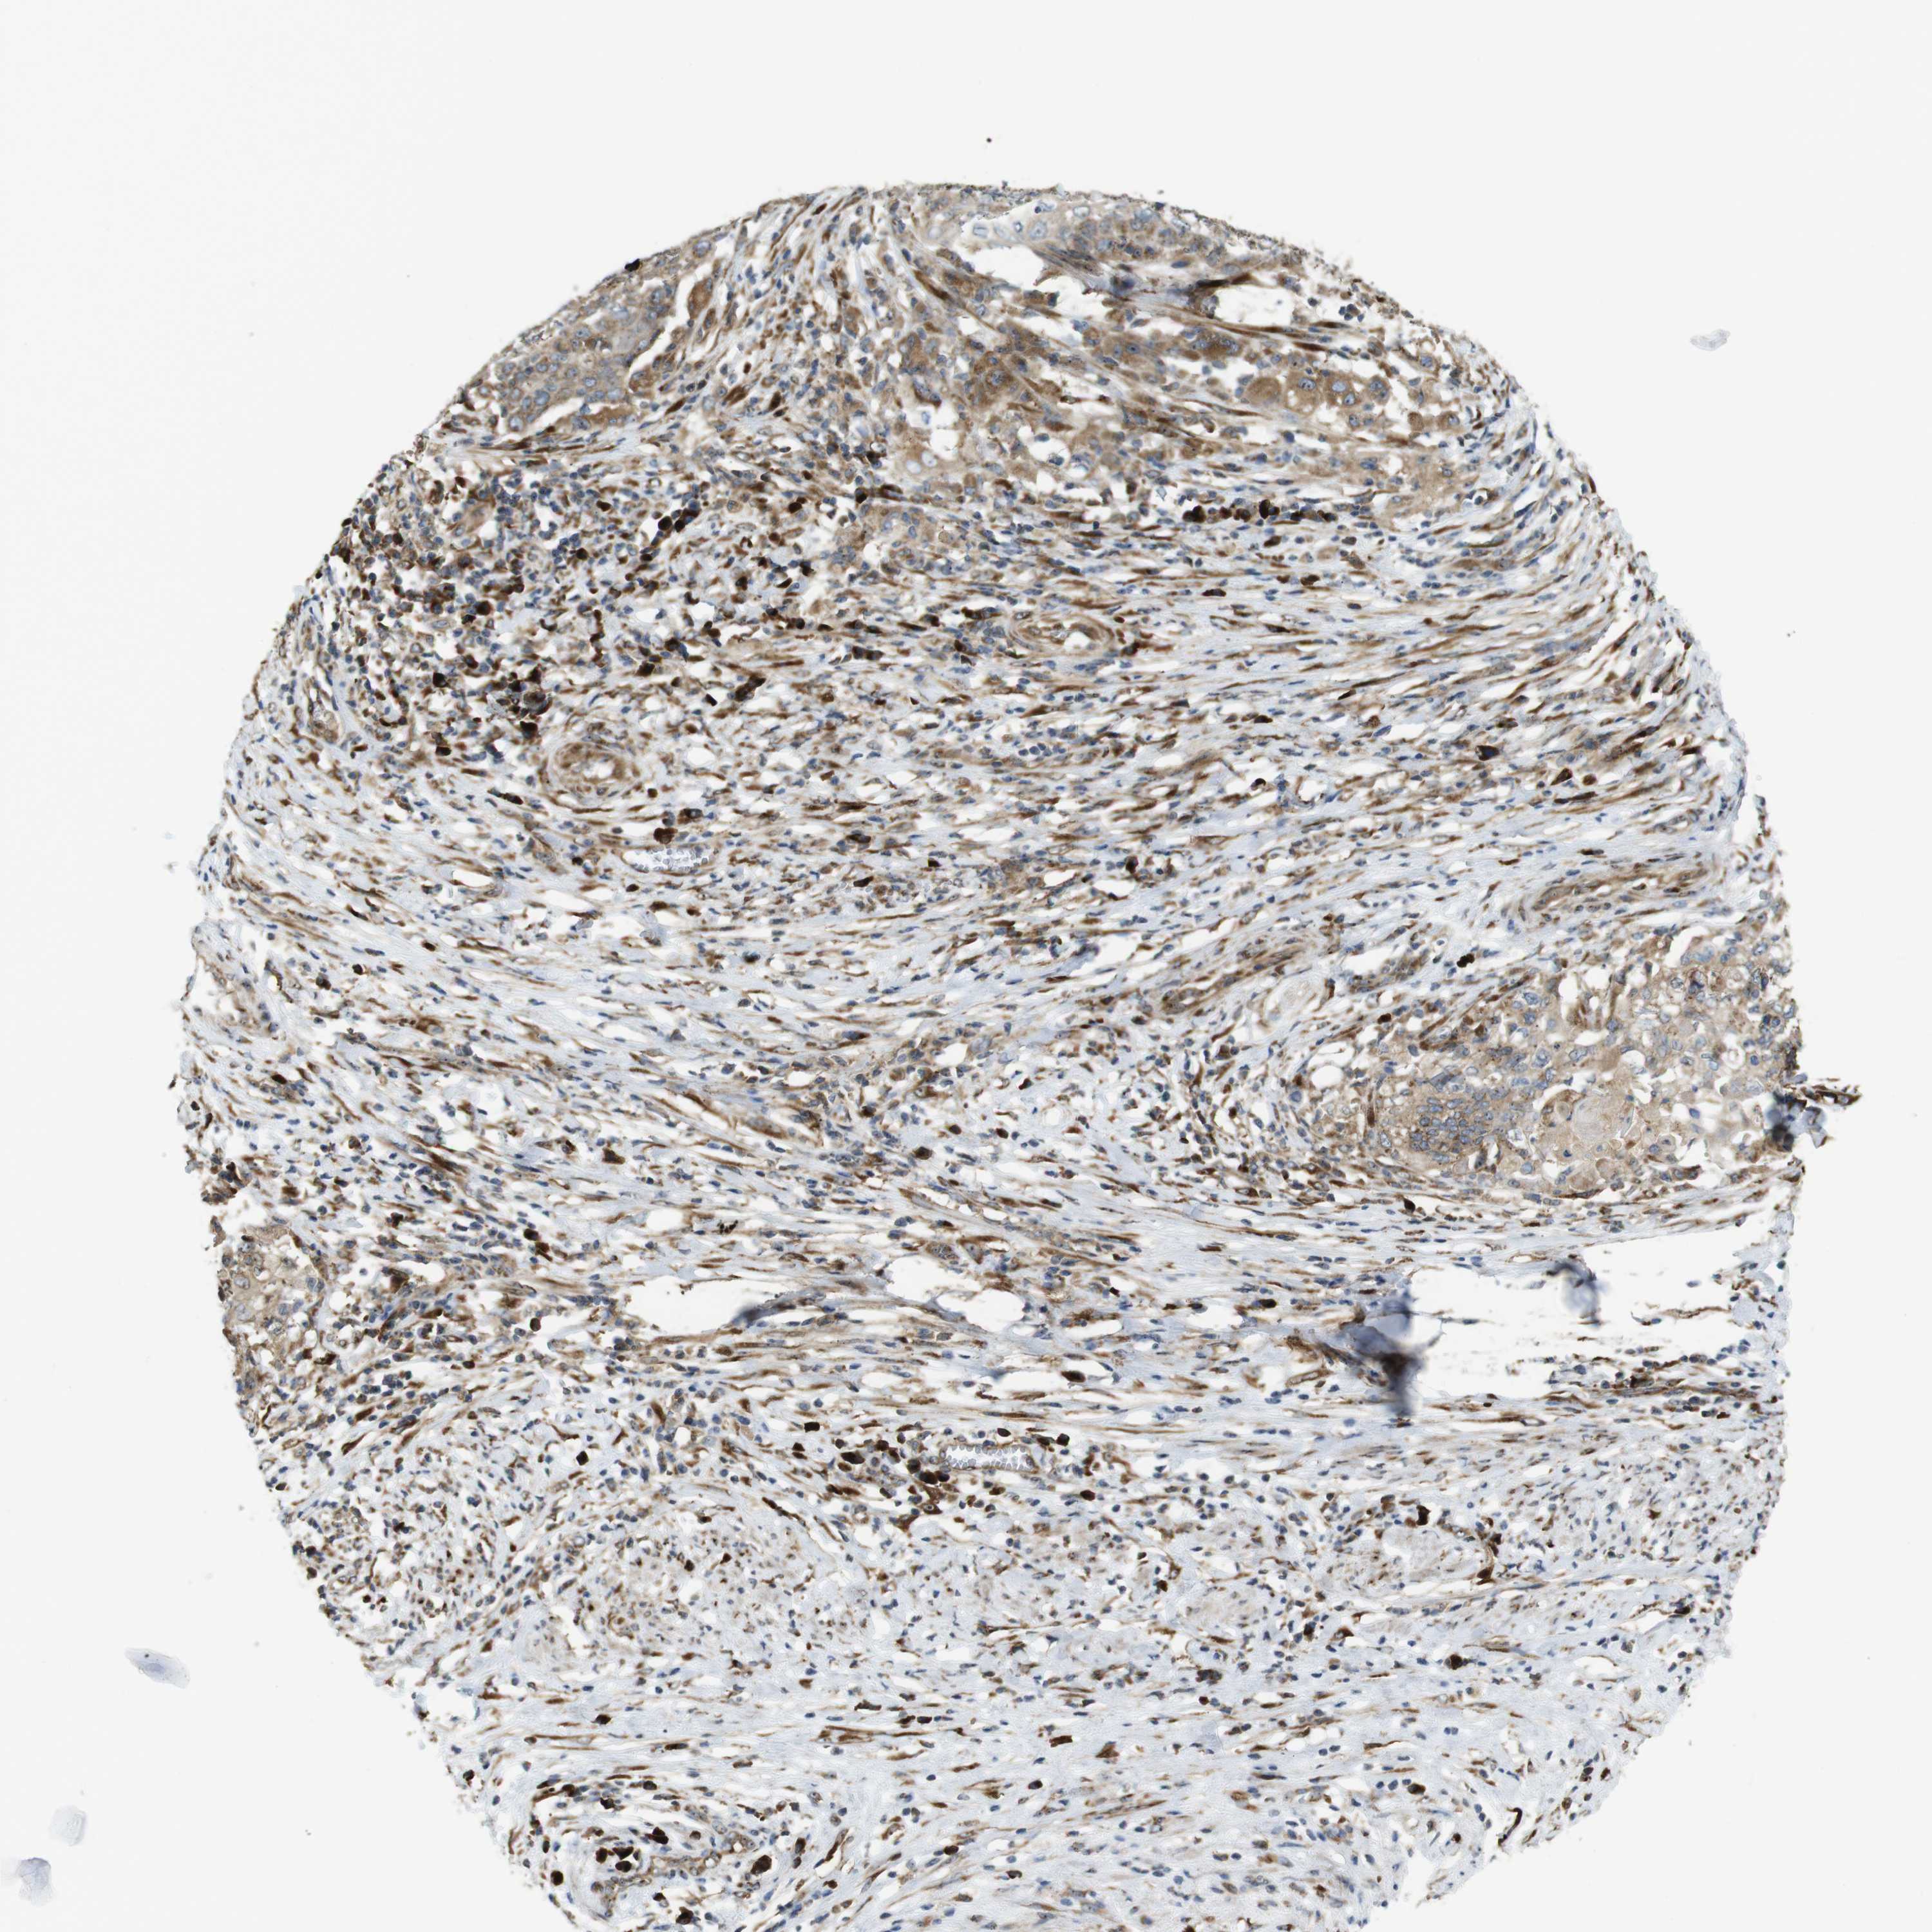

CERVICAL CANCER - Protein expressioni

A mouse-over function shows sample information and annotation data. Click on an image to view it in a full screen mode. Samples can be filtered based on level of antibody staining by selecting one or several of the following categories: high, medium, low and not detected. The assay and annotation is described here.

Note that samples used for immunohistochemistry by the Human Protein Atlas do not correspond to samples in the TCGA dataset.

Antibody stainingi

Antibody staining in the annotated cell types in the current human tissue is reported as not detected, low, medium, or high, based on conventional immunohistochemistry profiling in selected tissues. This score is based on the combination of the staining intensity and fraction of stained cells.

Each image is clickable and will lead to virtual microscopy that enables deeper exploration of all samples and also displays staining intensity scores, fraction scores and subcellular localization as well as patient and tissue information for each sample.

Antibody HPA014476

Antibody HPA058645

Staining

High

Medium

Low

Not detected

Intensity

Strong

Moderate

Weak

Negative

Quantity

>75%

75%-25%

<25%

None

Location

Nuclear

Cytoplasmic/membranous

Cytoplasmic/membranous,nuclear

Squamous cell carcinoma, NOS

Adenocarcinoma, NOS